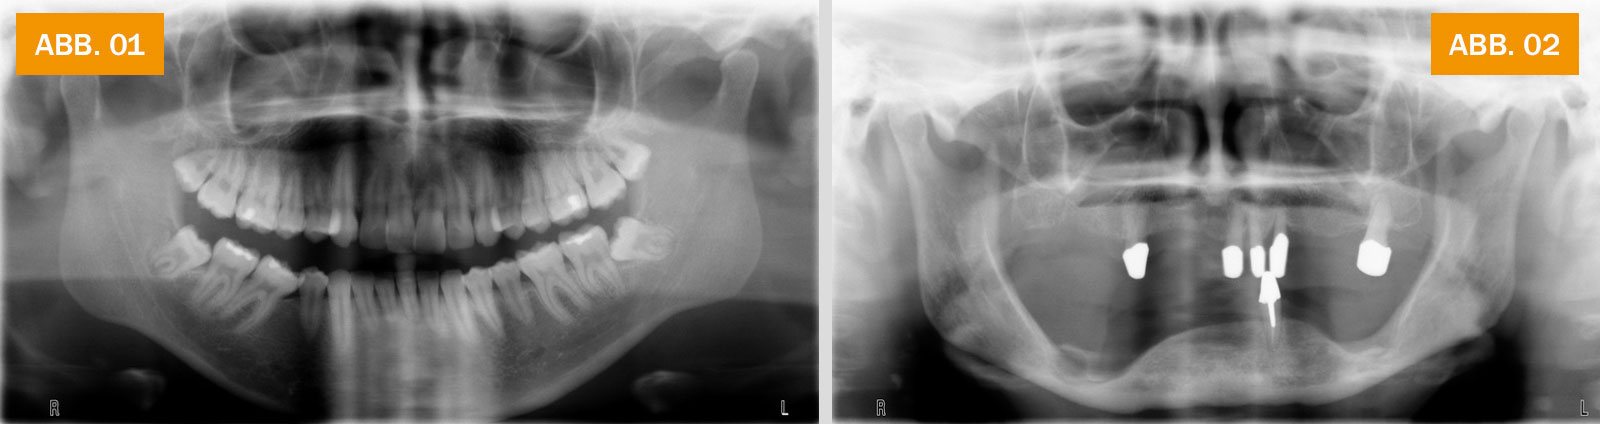

ABB. 01: Röntgenbild eines Jugendlichen mit voll bezahntem Ober- und Unterkiefer. Die Kieferknochen werden ständig belastet und sind stark ausgebildet.